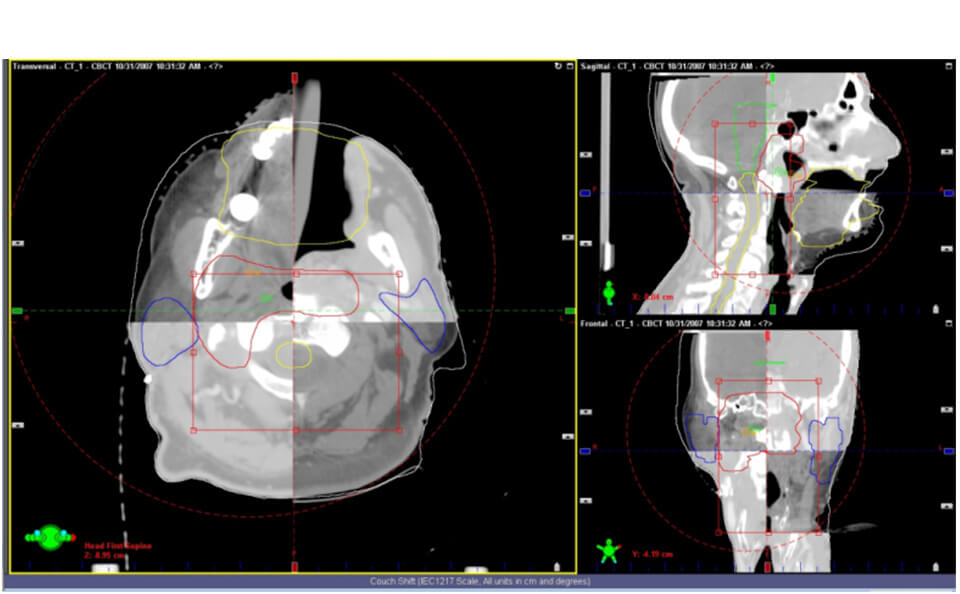

IGRT(画像誘導放射線治療)

治療装置に搭載されているOBI(ON BOAR IMAGE)でkV−X線画像を撮影し、その画像と治療計画CT画像から再構成された画像と位置合わせをします。また、CBCT(コーンビームCT)撮影を⾏い、照射位置微調整し位置精度を向上させます。これにより、正常な組織に放射線が当たることを最⼩限にします。

-

CBCT画像と計画CT画像との位置合わせ

CBCT画像と計画CT画像との位置合わせ